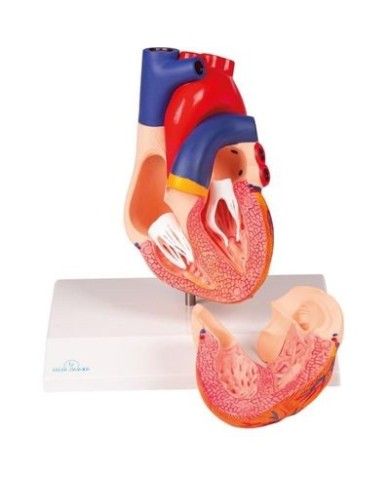

Fra i modelli di base segnaliamo il modello di cuore classico in due parti, in cui le due metà del cuore sono tenute insieme da potenti magneti.

Inoltre nella categoria sono presenti anche i modellini anatomici di cuore con bypass e con sistema di conduzione, fino ai modelli anatomici comparativi di patologie del cuore.

Per una migliore comprensione delle strutture anatomiche del cuore sono stati realizzati anche dei modelli anatomici di cuore ingrandito, si va dai piccoli ingrandimenti fino ai modelli di cuore per la formazione in aula, come il modello anatomico di cuore gigante prodotto da 3B Scientific: un modello di cuore ingrandito di ben otto volte.